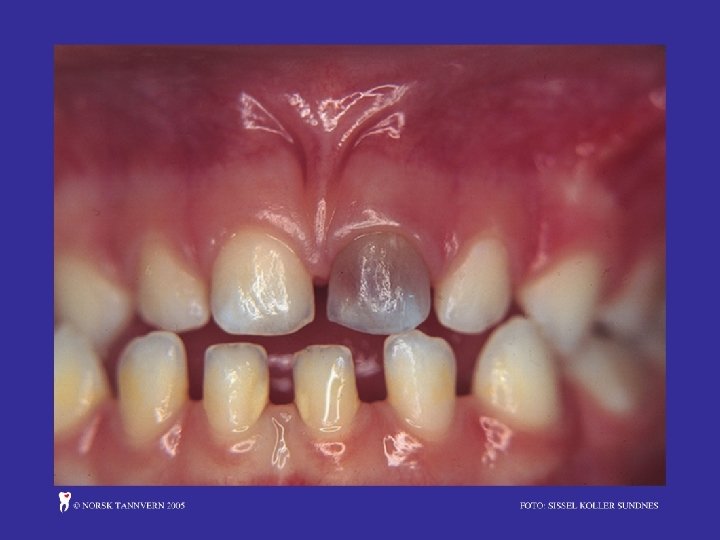

Karies (tannråte) Barnebelegg

Barnebelegg:

• Se på tannfrembrudd, alle fortenner i overkjeve og underkjeve? Jeksler kommer normalt seinere. • Løft ut/opp leppe og se etter synlig belegg på framsida av tennene, bruk en spatel, evt. den butte sida av en tannpirker, skrap langs tannkjøttkanten. • Instruer i tannpuss to gr. pr. dag • Vurder henvisning til tannhelsetenesta dersom problem med utføring av tannpuss og synlige mengder belegg • Vurder også henvisning ved andre munnproblem • Oppfølging av kosthald og tannpuss som ved 8 og 10 mnd. • BILDE OG PUSSEINSTRUKSJON!!!